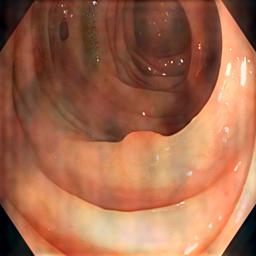

As Fig. 2(c) shows, background inference (shadows) is introduced by the Fourier-Transform-Based domain generalization. In our ICASSP-2024 study [25], we applied soft-thresholding (ST) filtering to minimize background interference in retinal fundus image segmentation. Soft-thresholding, a widely recognized technique in signal processing and statistical estimation, promotes sparsity and enhances data quality [26, 27]. By applying a threshold to the DFT coefficients, it effectively reduces noise and irrelevant details while preserving essential features. The soft-thresholding function operates for a given threshold as follows:

where is the input and is the threshold value. However, when we applied the same domain generalization method [25] on the polyp dataset, we notice that the soft-thresholding function enhances noisy patterns while eliminating the shadows caused by the target background, as Fig. 2(d) present. This is because the soft-thresholding function shrinks all coefficients (both large and small) toward zero. This introduces bias in the retained large coefficients, potentially distorting important features.

As Fig. 2(d) reveals, applying hard thresholds removes shadows caused by the amplitude swapping without producing noisy patterns, but it may smooth the synthetic images.